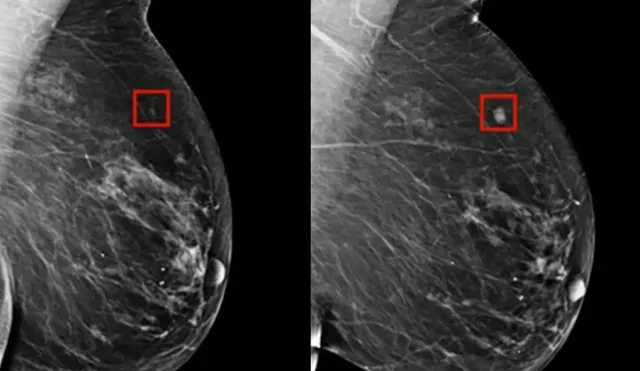

Një program i ‘AI’ zbuloi me sukses kancerin e gjirit tek një grua katër vjet përpara se të zhvillohej.

Dr. Larry Norton i Qendrës së Gjirit Lauder shpjegoi për CNN se ‘AI’, e cila ka ekzistuar që nga fundi i viteve 1990, po bëhet më e dobishme në identifikimin e problemeve të mundshme shëndetësore. AI mund të ndihmojë radiologët duke identifikuar zonat në mamografi që kanë nevojë për ekzaminim më të afërt.

Sidoqoftë, AI ka për qëllim të ndihmojë, jo të zëvendësojë, profesionistët e mjekësisë njerëzore. Mund të zvogëlojë ngarkesën e punës së radiologëve me 30% dhe të rrisë shkallët e zbulimit të kancerit me 13%, sipas New York Times. AI është përdorur gjithashtu me sukses për të zbuluar kancerin e mushkërive.